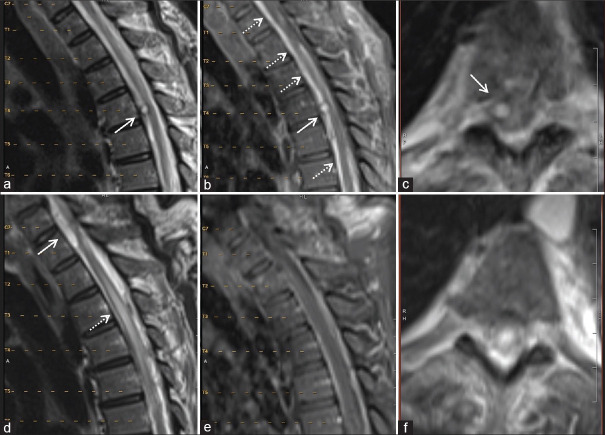

Spinal arachnoid web (AW) is a rare condition causing spinal cord-related issues. Its cause is often idiopathic but can be linked to past trauma or spine surgery. We describe two cases of AWs that developed after subarachnoid hemorrhage (SAH). Case #1 is a 71-year-old male with nonaneurysmal SAH who developed myelopathy 1 year later. Magnetic resonance imaging revealed upper thoracic cord edema and an AW. Case #2 is a 57-year-old female who underwent coiling of a ruptured basilar artery aneurysm and ventriculoperitoneal shunting for hydrocephalus. Twenty months later, she developed mid-thoracic AW requiring surgical resection. Both patients showed symptom improvement postresection avoiding further reoperation. History of SAH is emerging as a risk factor for AW development, emphasizing the importance of monitoring delayed-onset myelopathy and back pain in recent SAH patients.

脊髓蛛网膜(AW)是一种罕见的疾病,会引起脊髓相关问题。其病因通常是特发性的,但也可能与过去的创伤或脊柱手术有关。我们描述了两例在蛛网膜下腔出血(SAH)后出现的蛛网膜瘤。病例1是一名71岁的男性,患有非动脉瘤性SAH,1年后出现脊髓病变。磁共振成像显示上胸段脊髓水肿和 AW。病例 2 是一名 57 岁的女性,因脑积水接受了基底动脉瘤破裂的盘绕手术和脑室腹腔分流术。20 个月后,她患上了中胸 AW,需要进行手术切除。两名患者在切除术后症状均有所改善,避免了再次手术。SAH史正在成为AW发病的一个危险因素,这强调了监测近期SAH患者迟发性脊髓病和背痛的重要性。